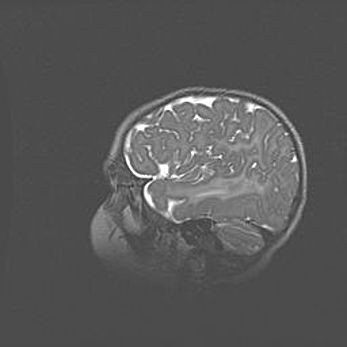

Церебральная ишемия II.

Возраст: 5 дней

Вес: 3400 г

Пол: женский

Окружность головы: 35 см

Срок гестации: 39 недель

Церебральная ишемия – это заболевание, характеризующееся недостаточностью (гипоксией) либо полным прекращением (аноксией) снабжения мозга кислородом по причине закупорки одного или нескольких сосудов. Это приводит к  что метаболическим расстройствам различной степени тяжести в тканях головного мозга, развитию коагуляционных некрозов и гибели нейронов.